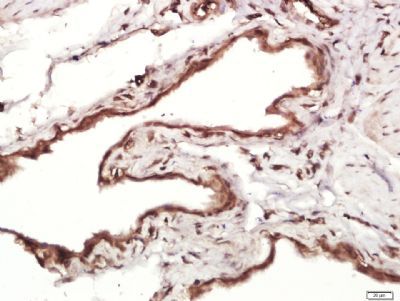

MMRN1 Rabbit Polyclonal Antibody

MMRN1

KLH conjugated synthetic peptide derived from human MMRN1 (851-950/1228aa)

别名:ECM; Elastin microfibril interface located protein 4; Elastin microfibril interfacer 4; EMILIN 4; EMILIN4; Endothelial cell multimerin 1; Glycoprotein Ia; GlycoproteinIa; GPIa; MMRN 1; MMRN; Multimerin 1; Multimerin-1; Multimerin1; MMRN1_HUMAN.

免疫原:KLH conjugated synthetic peptide derived from human MMRN1 (851-950/1228aa)

预测反应性:Bovine, Canine, Equine, Human, Mouse, Rat, Sheep

分子量:136 kDa

应用稀释比例:ELISA=1:5000-10000